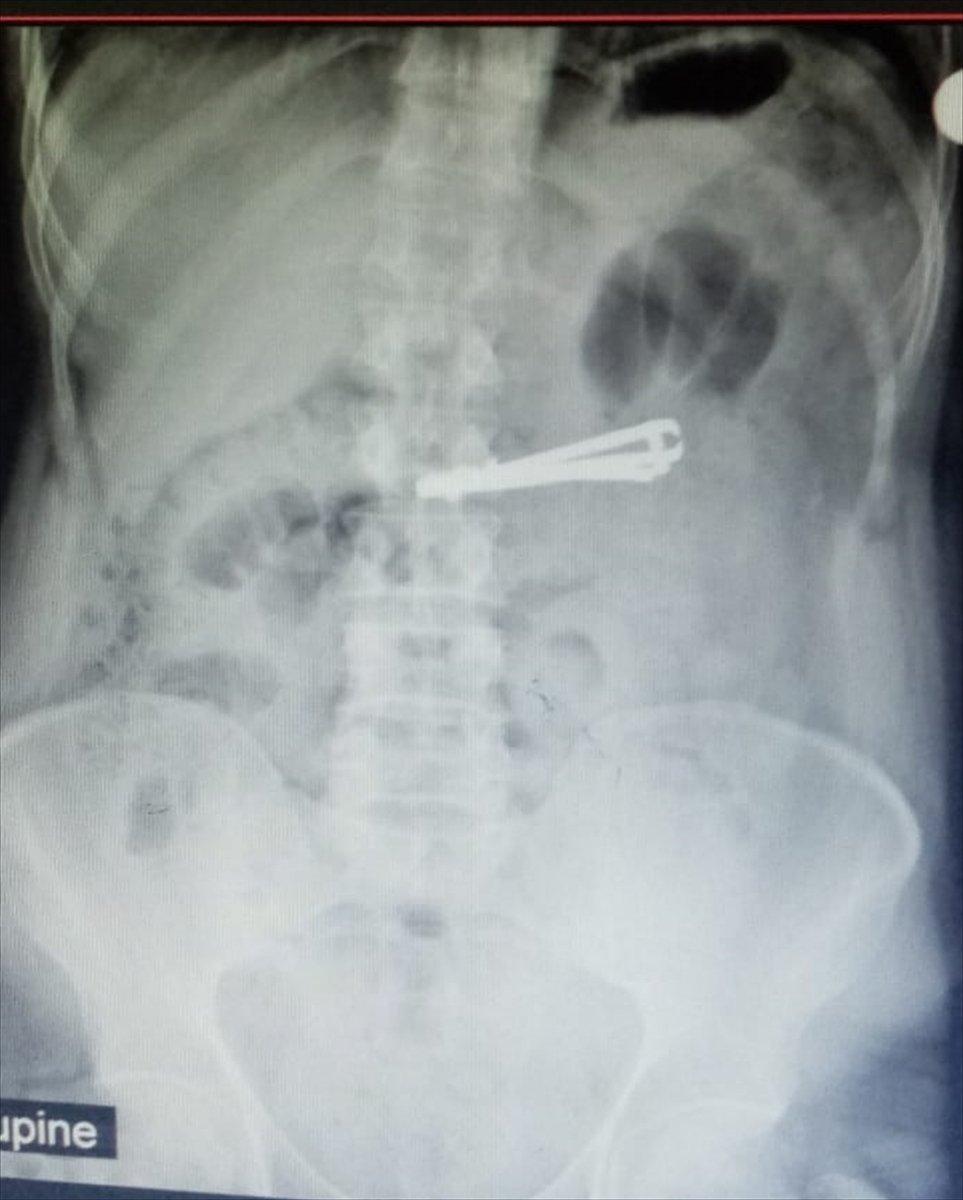

Siirt'in Kurtalan ilçesinde yaşayan ve doğuştan ağır mental retardasyon (zeka geriliği) hastası 42 yaşındaki Mutih Akurt, elindeki tırnak makasını yuttu.

Hastanın midesindeki tırnak makası, Genel Cerrahi Uzmanı Dr. Yasemin Küçük'ün yaptığı endoskopiyle çıkarıldı. Sağlığına kavuşan Akurt, daha sonra taburcu edildi.